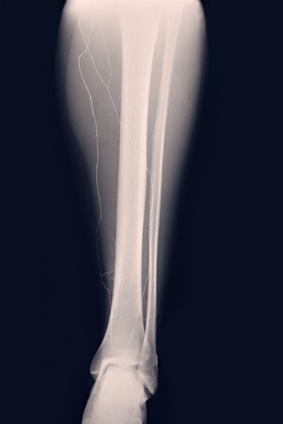

FRACTURA DE TIBIA POR ESTRES

Una grieta o solución de continuidad (fractura) en el hueso de la espinilla (tibia).

y tratar una fractura por estrés del hueso de la espinilla. Dicho profesional podrá hacer una resonancia magnética, una radiografía o un

escáner del hueso para ver el alcance de la lesión.